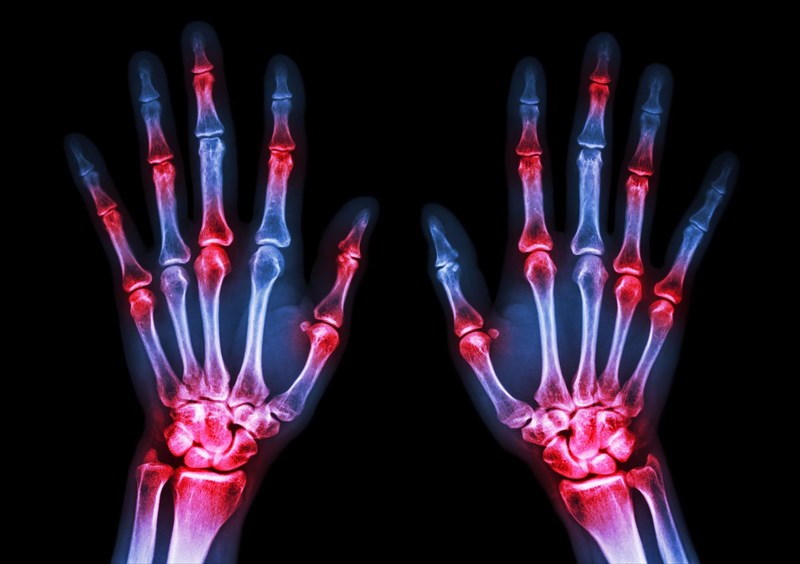

Does Arthritis Affect Every Joint . although osteoarthritis can damage any joint, the disorder most commonly affects joints in your hands, knees, hips and spine. Muscles and tissue around the joint are. arthritis is a common condition that causes pain and inflammation in a joint. osteoarthritis can affect any joint but is most common in the knees, hips, spine and small joints in the hands. In the uk, millions of people have arthritis or other,. when you have arthritis, movement can decrease your pain and stiffness, improve your range of motion, strengthen your. Its signs and symptoms typically show up more often in individuals. oa can affect any joint, but typically affects hands, knees, hips, lower back and neck. arthritis can affect any joint, but is most common in people’s:

although osteoarthritis can damage any joint, the disorder most commonly affects joints in your hands, knees, hips and spine. arthritis can affect any joint, but is most common in people’s: Its signs and symptoms typically show up more often in individuals. In the uk, millions of people have arthritis or other,. when you have arthritis, movement can decrease your pain and stiffness, improve your range of motion, strengthen your. oa can affect any joint, but typically affects hands, knees, hips, lower back and neck. arthritis is a common condition that causes pain and inflammation in a joint. Muscles and tissue around the joint are. osteoarthritis can affect any joint but is most common in the knees, hips, spine and small joints in the hands.